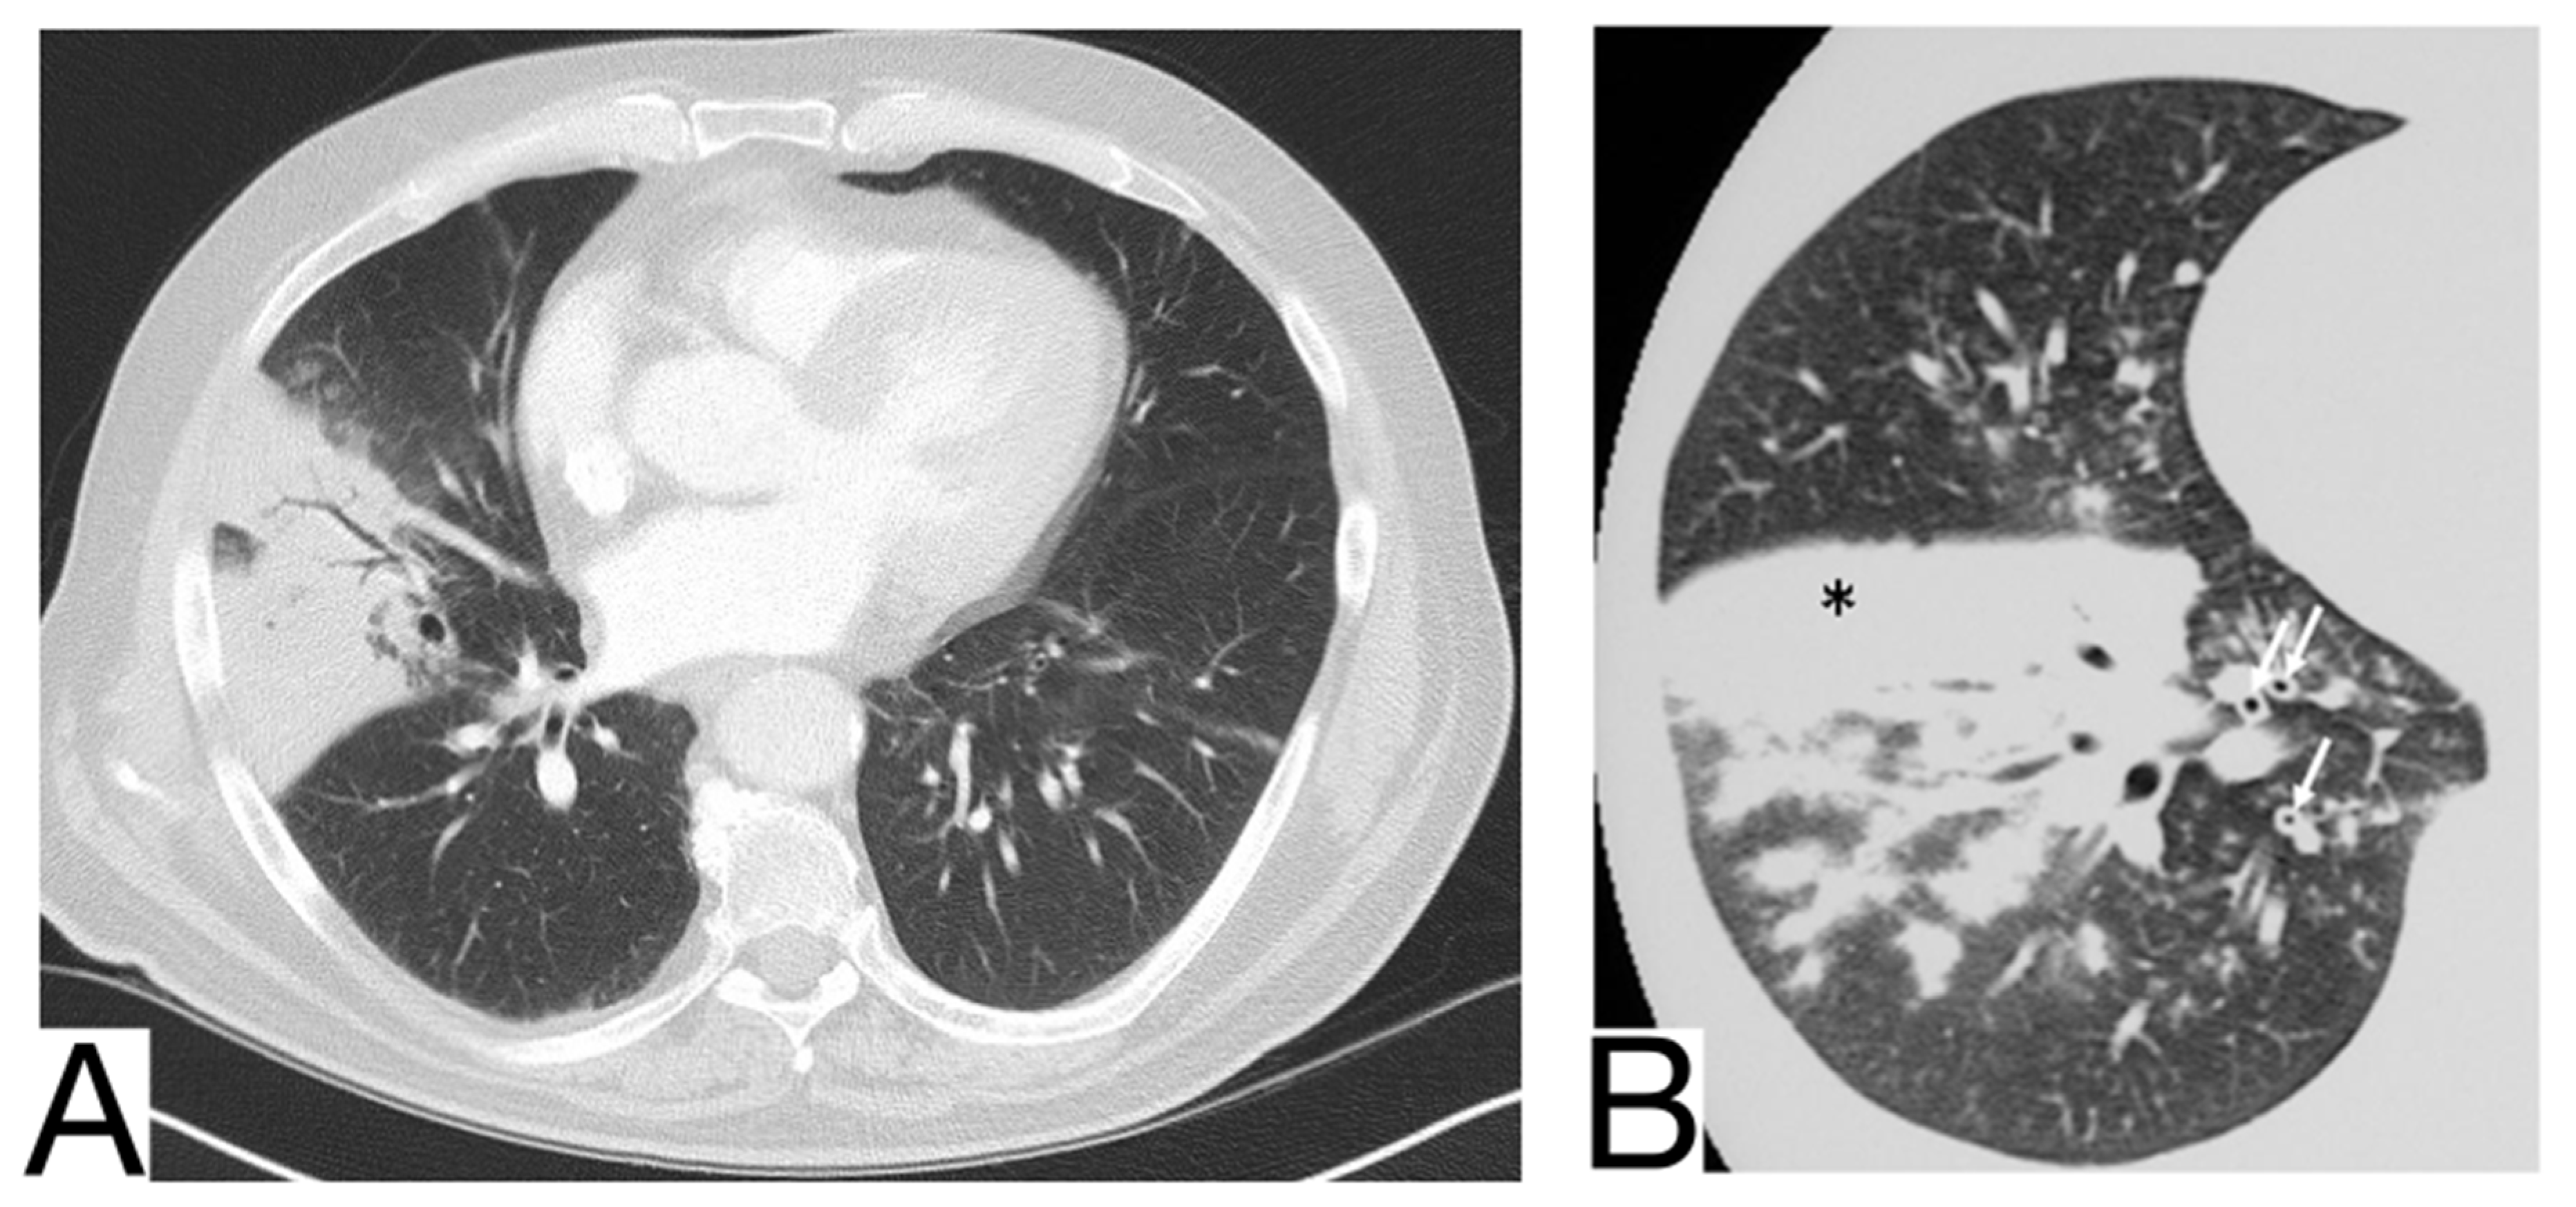

10.1. Bacterial Pneumonia

10.4. Aspergillosis